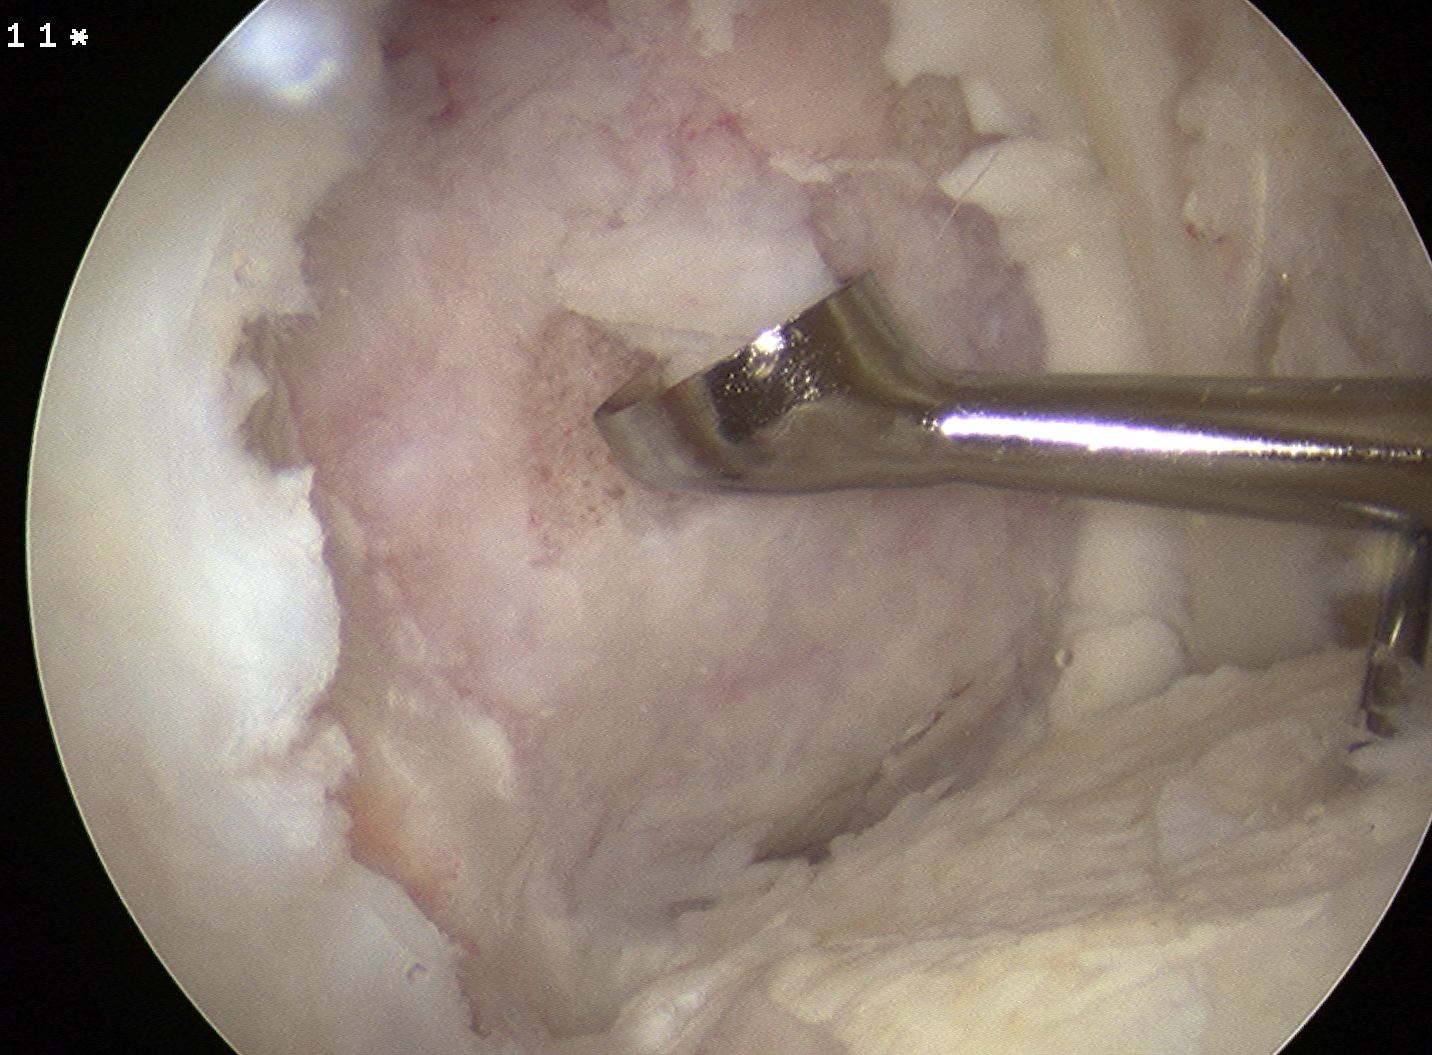

Take bone graft from medial tibia

- depends on amount of bony defect

- turn into paste / add blood

- put in small syringe that will fit through AM portal

- cut tip off

Use K wire to microfracture

- insert bone graft

- immediately reduce fragment

- secure with K wires for cannulated screws

ORIF

In this case, 2 x Arthrex bioabsorble screws used

- drill and tap over wire

- remove wire

- insert screw and bury head